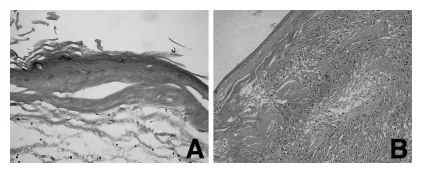

组织学检查显示,囊肿与小脑实质分界清晰,未见侵袭性生长。囊壁内衬扁平鳞状上皮,无不典型性,上皮下的纤维组织高度玻璃样变。囊腔内充满大量角化物质。未见未成熟神经组织等其他成分(图5A)。部分囊壁可见异物反应和淋巴细胞浸润(图5B)。患者术后恢复平稳,出院时无神经功能缺损。

图5,显微照片显示:A硬膜下部分囊壁内衬扁平鳞状上皮,囊腔充满大量角化碎屑;B硬膜外囊壁可见异物巨细胞反应及淋巴细胞浸润。(苏木精-伊红染色,A:×200,B:×20)